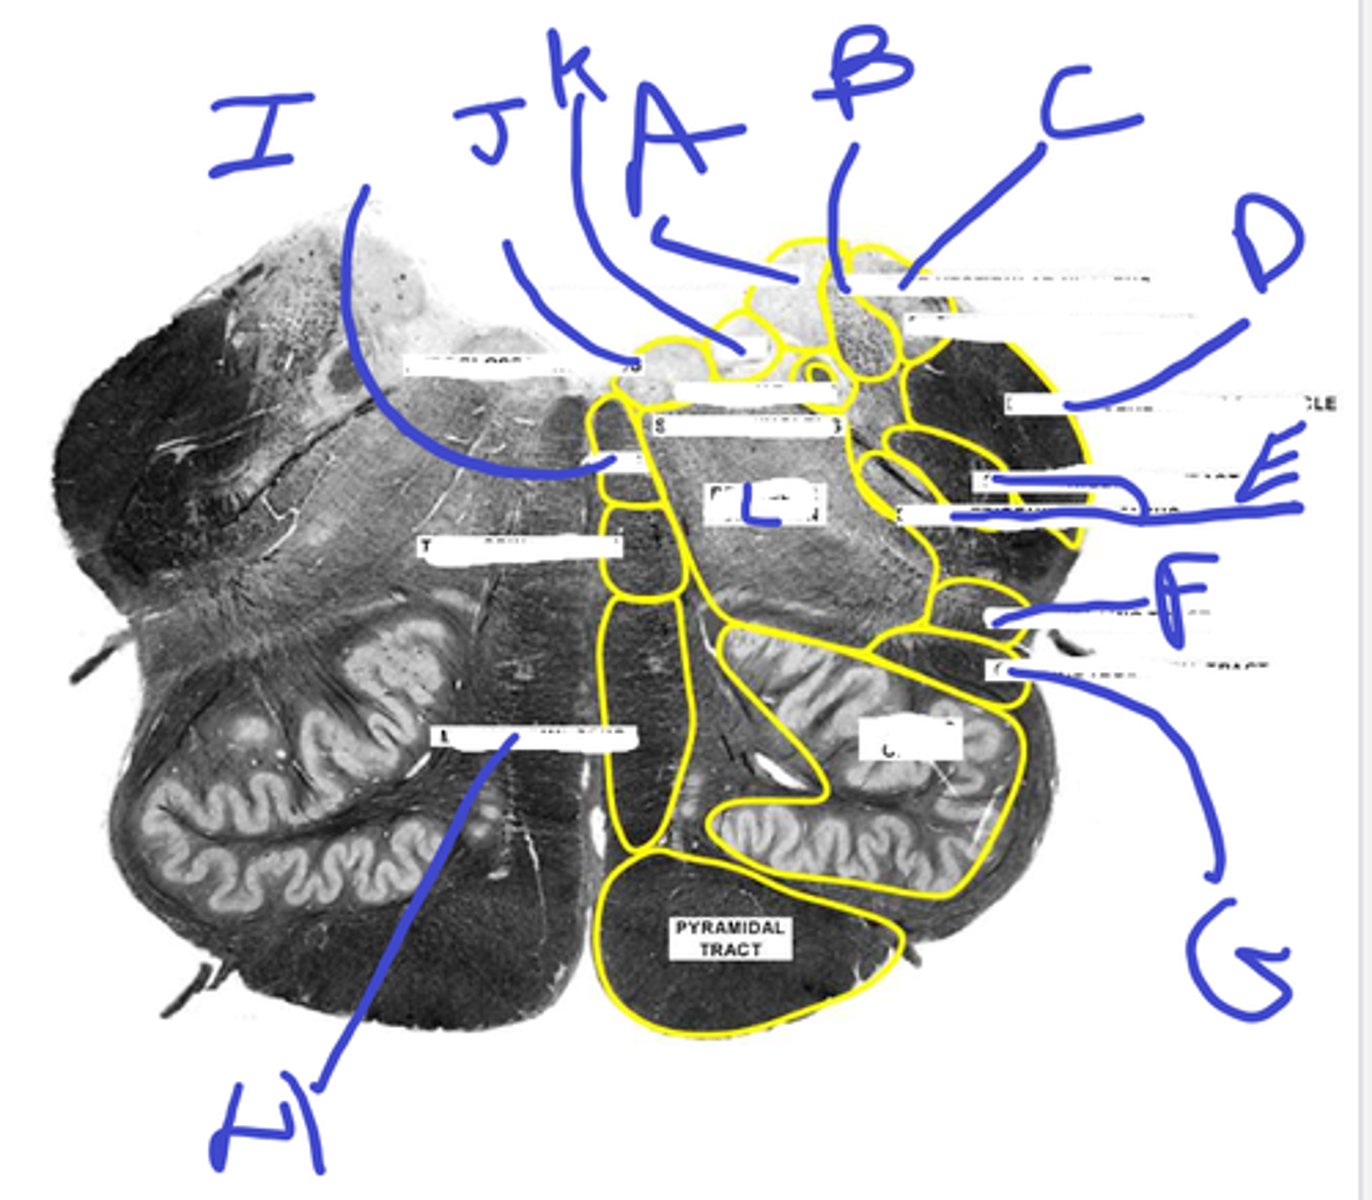

a-med vest nuc

b-inf vest nuc

c-ext cuneate nuc

d-inf cerebellar ped

e-spinal trigem tract/nuc

abcde

f-spinothalamic

g-central tegmental

h-medial lemniscus

i-mlf

j-hypoglossal

k-dmx

l-reticular formation

f-l